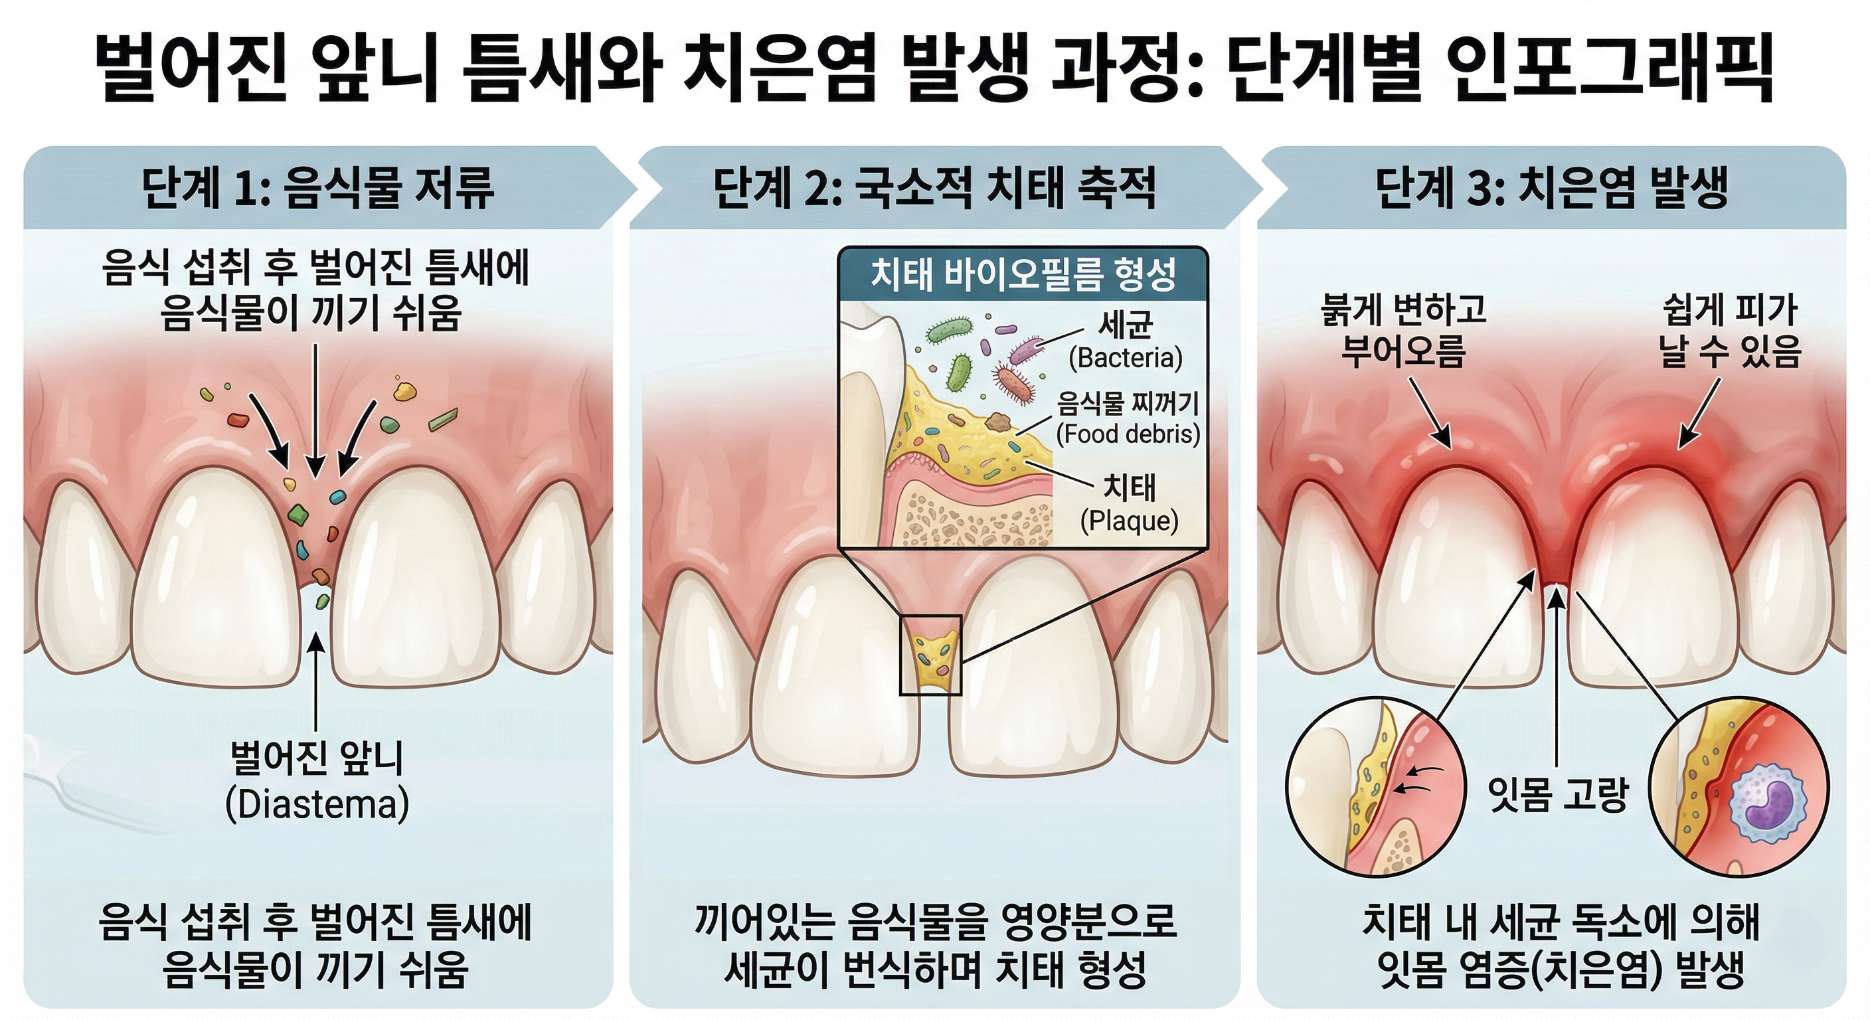

2. 방치하면 잇몸 건강까지 위협받을 수 있습니다

소중한 내 치아, 공포 마케팅에 휘둘리지 마세요! 틈새가 조금 벌어져 있다고 해서 당장 치아가 흔들리고 빠지는 것은 절대 아닙니다. 하지만 이를 단순한 미용상의 콤플렉스로만 가볍게 여겨 오랜 기간 방치할 경우, 벌어진 공간 사이로 음식물 찌꺼기가 지속적으로 저류하게 됩니다.

이는 칫솔질만으로는 완벽히 제거하기 힘든 국소적인 치태와 치석 축적을 유발하여 결국 잇몸뼈를 녹이는 치주염으로 이어질 수 있으므로, 적절한 시기에 공간을 폐쇄해 주는 것이 평생의 구강 건강 유지에 훨씬 유리합니다.